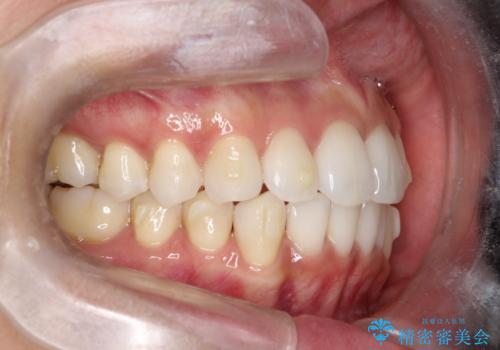

【インビザライン】前歯の凸凹をIPRで改善

- 前歯の凸凹を主訴に来院されました。

前歯を並べるために歯と歯の間にヤスリを入れてわずかに歯を削ることでスペースを確保しています。

歯と歯の間にヤスリを入れてわずかに歯を削ることでスペースを確保する処置をIPRと呼びます。

当院では拡大鏡を用いて丁寧に処置することで歯冠形態を損なわずに行うことができます。